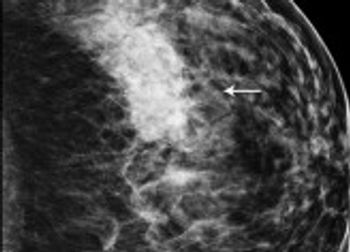

Integrating 2D and 3D screening increases breast cancer detection and may lower reports of false positives.

Three-dimensional imaging with breast tomosynthesis increases diagnostic accuracy and reduces false positive recall rates.